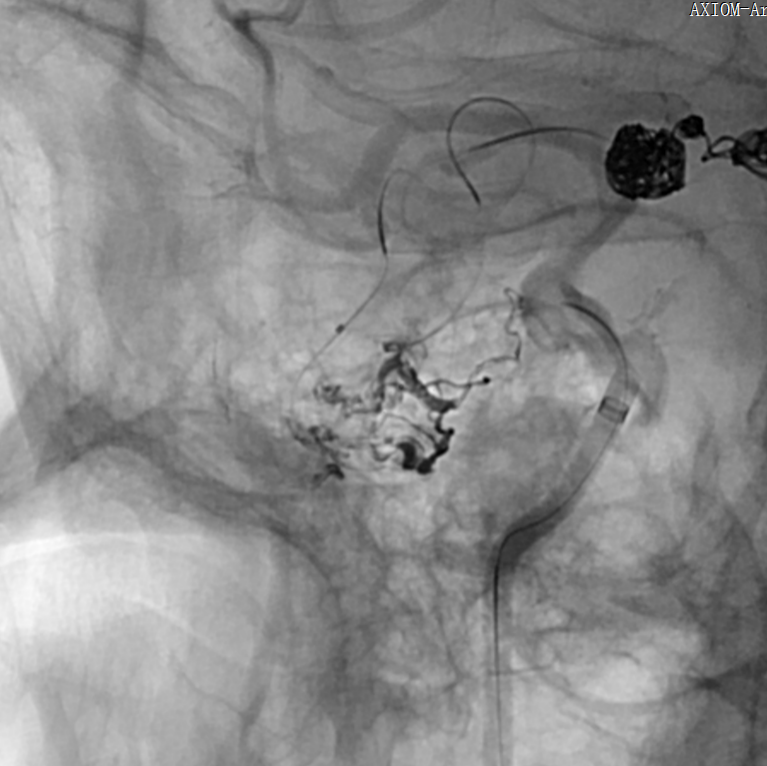

入院后脑血管造影检查提示:右侧颞叶动静脉畸形,由右侧大脑中动脉两分支血管参与供血,右侧大脑后动脉一分支血管参与供血,畸形团大小约1.1*1.3cm,通过侧裂静脉经皮层静脉引流入上矢状窦前部;并可见右侧大脑后动脉供血畸形团的分支血管血流相关性动脉瘤两枚。

先行血管内介入栓塞畸形团或闭塞供血动脉远端,然后开颅手术切除畸形团。其中介入栓塞优先处理血流相关性动脉瘤,采用弹簧圈填塞动脉瘤,然后用Onyx胶栓塞畸形团或闭塞供血动脉远端。

1. 通过椎动脉先将Echelon 10微导管在导丝导引下超选至远端动脉瘤,填塞弹簧圈(Cosmos 4mm/12cm,Jasper 3.5mm/10cm,Axium 3mm/8cm,Jasper 2.5mm/8cm),然后逐渐回撤微导管至近端动脉瘤填塞(Axium Prime 4mm/12cm),最后可见向畸形团供血明显减弱,远端动脉瘤不显影,近端动脉瘤仍有显影。

将Echelon 10微导管超选至右侧大脑中动脉分叉部分支血管远端,微导管造影确认系畸形团供血动脉,DMSO冲管后注射Onyx胶再行造影,可见该分支血管远端闭塞,予以撤出Echelon 10微导管。

用Apollo微导管超选大脑中动脉M1段分支血管直至畸形团内,进行微导管造影确认微导管进入畸形团,DMSO冲管,缓慢注射Onyx 18,路图下可见胶在畸形团内弥散,最后颈内动脉造影可见畸形团完全不显影,但是胶反流导致拔管困难,透视下可见血管移位变形明显。